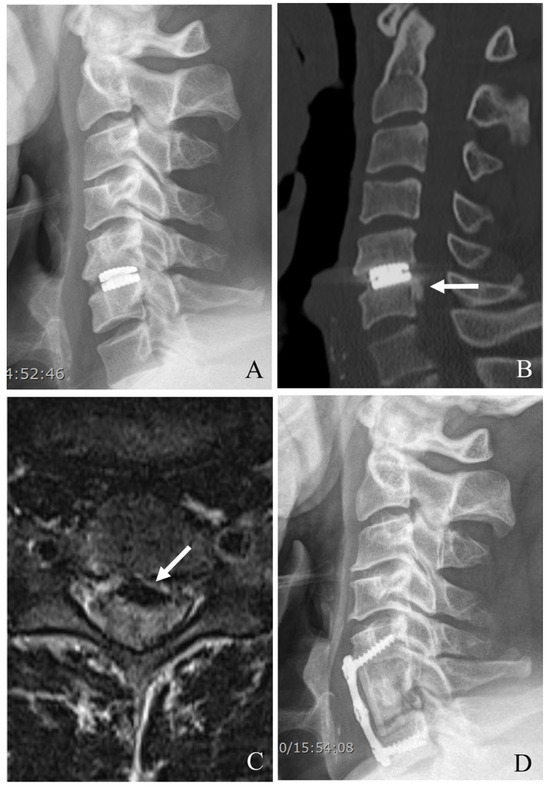

Figure 3. Plain X-rays (A), computed tomography (B), and magnetic resonance image (C) showing cervical disc arthroplasty at C5–6 and C6–7 and severe foraminal stenosis and posterior osteophytes (white arrows). The patient underwent C4–7 posterior cervical laminectomy, foraminotomy, and fusion with C3–7 pedicle screw fixation (D).

When CDA fails at the index level, PCDF is a well-established surgical option, particularly in cases where anterior reoperation is either contraindicated or insufficient [22,23,24,25,26]. PCDF provides robust neural decompression and stabilization, making it especially useful for cases with instability, deformity, or posterior element involvement (Figure 3). Although this approach is more invasive than anterior reoperations, it offers comprehensive management of those with complex failure mechanisms.